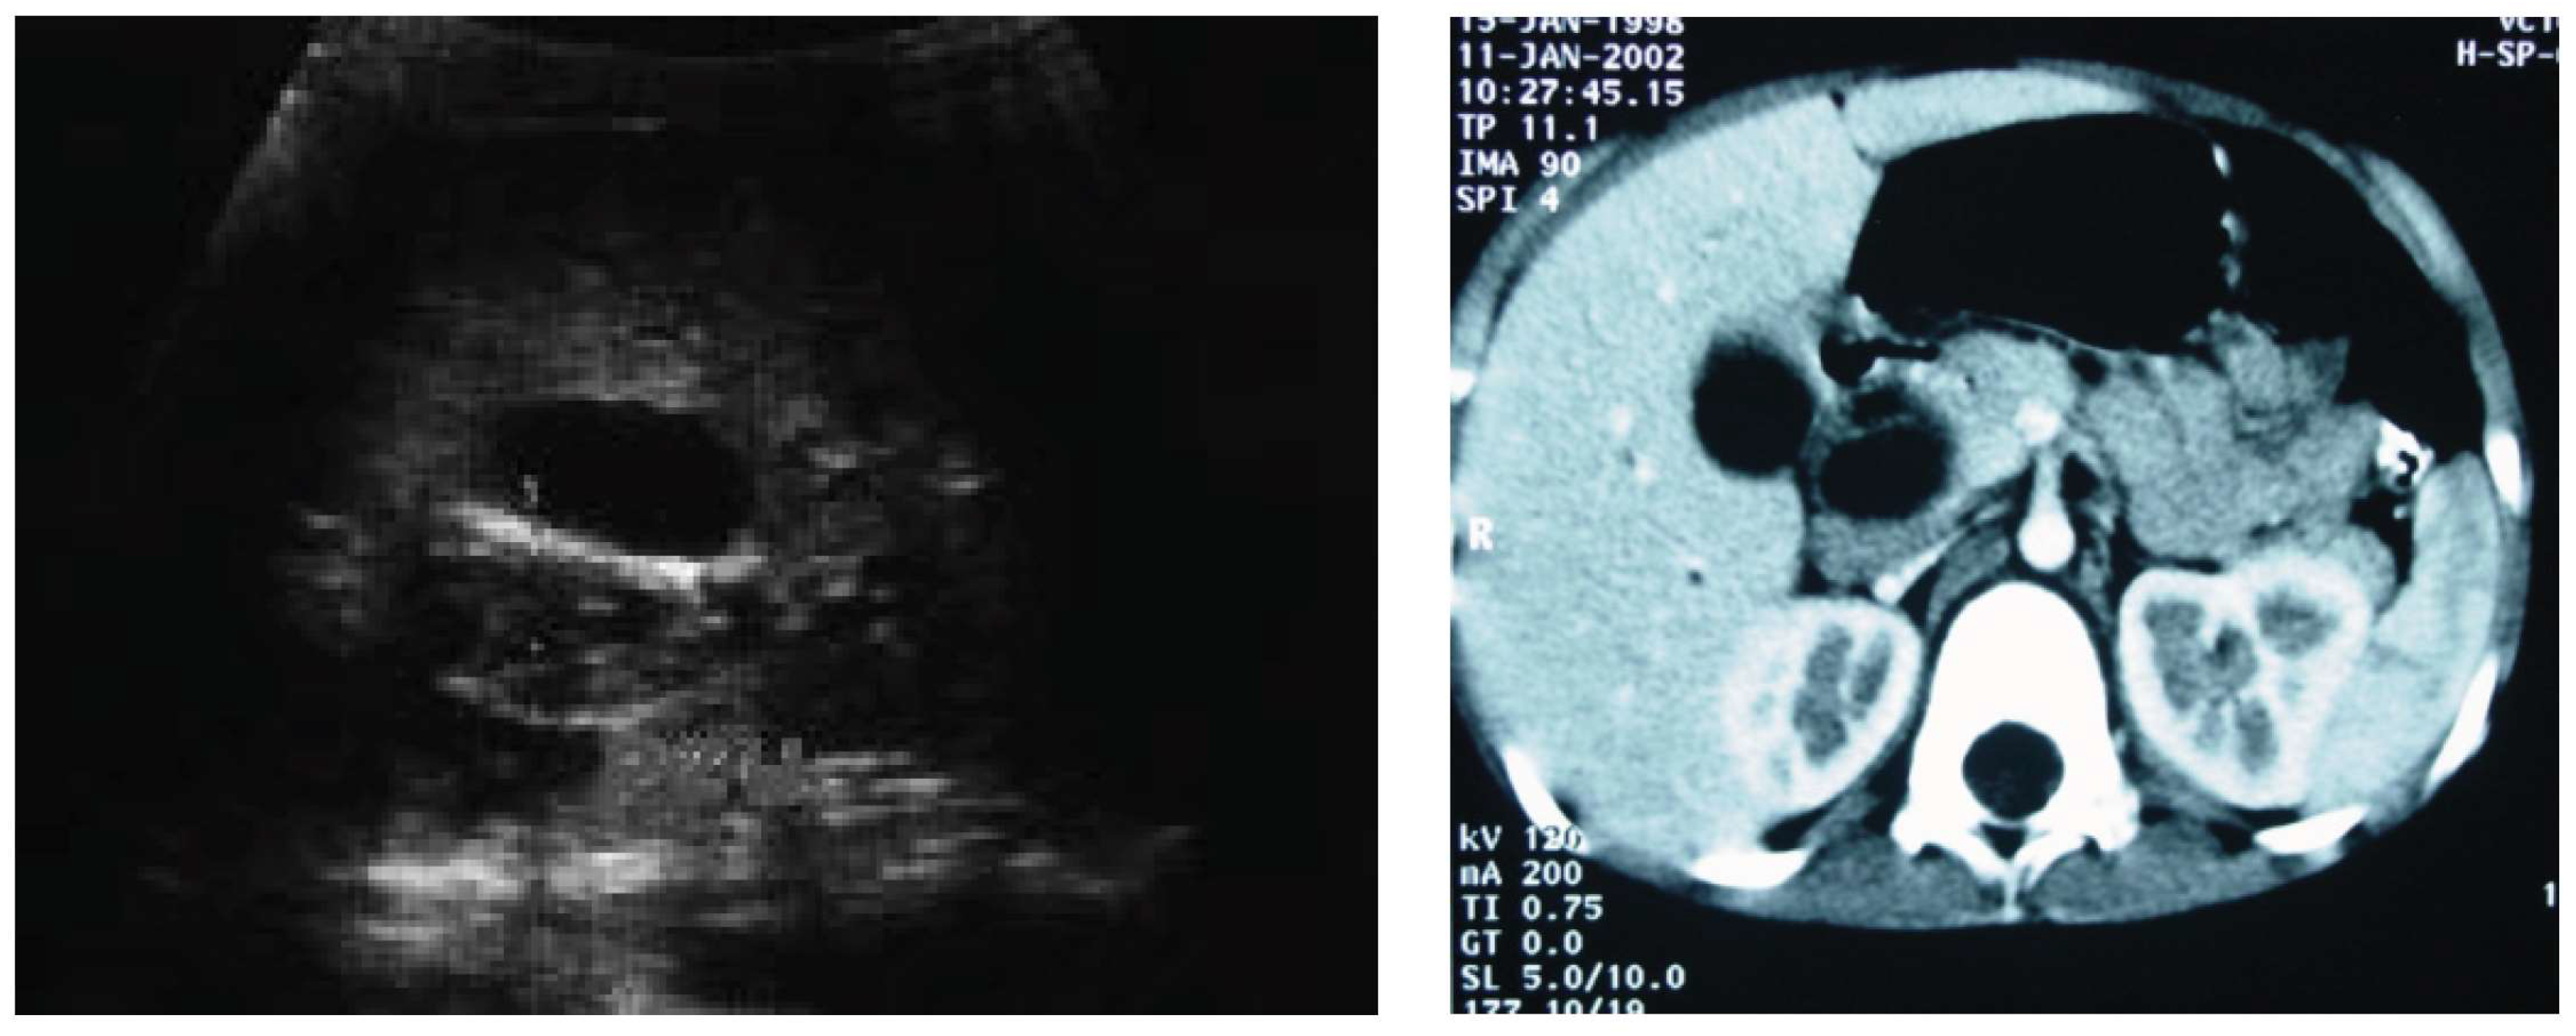

Due to the rarity of biliary RMS, its most common symptom—obstructive jaundice—may be taken for other entities such as choledochal malformation, choledocholithiasis, cholangitis or pancreatic tumor. In our series, only two patients had an upfront diagnosis of a tumor; for the remaining patients, other conditions were misidentified initially. The suspicion of a bile duct tumor was eventually raised in all these children after admission to our center. This issue is also raised by other authors [4,5]. One of our patients diagnosed with gallstone disease underwent laparoscopic cholecystectomy. She was treated for persistent obstructive jaundice for 2 months before the correct diagnosis was made. Another patient was diagnosed with a bile duct cyst, and thus, she was qualified for choledochal cyst resection surgery. When retrospectively analyzing imaging studies of this girl, we found that despite both ultrasound and computer tomography being strongly suggestive of a bile duct cyst, scintigraphy did not provide such confirmation, failing to show a clear image of the cyst (Figure 1 and Figure 2). Such clinical situations may lead to the performance of primary resection, which is rarely a complete one (R0) [1,7,11]. Thus, in the differential diagnosis of bile duct cysts and obstructive jaundice in children, biliary RMS must always be considered. All our patients manifested obstructive jaundice as the first symptom of disease, which was reported in 60–80% of patients in other studies [3,4,19].

Figure 1. Ultrasound and computed tomography in a patient with biliary tract RMS who was incorrectly diagnosed with a bile duct cyst—cystic dilation of the common bile duct up to 2 cm, filled with thick bile, and dilation of intrahepatic bile ducts.